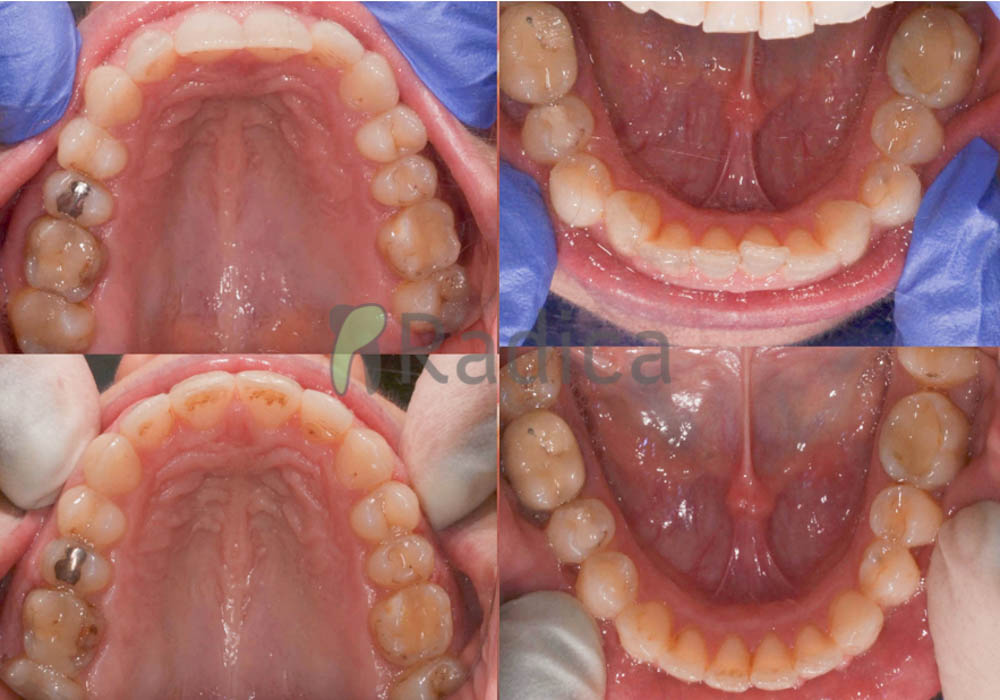

U sljedećem primjeru su se na mjesto donjih ekstrahiranih prvih molara stavili dentalni implantati prije ortodontske terapije (rad dr. Gorana Radice) i ujedino su služili za pojačenje sidrišta tijekom ortodontske terapije. Nakon ortodontske terapije estetski su se preoblikovali sjekutići i napravile nove krunice (također rad dr. Gorana Radice).